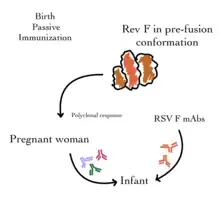

Addressing the more challenging aspect, the need for a newborn vaccine, researchers employed a pregnancy-administered approach to protect infants during the first six months, a critical period for RSV susceptibility. [40] The FDA's advisory committee endorsed Pfizer's parental RSV vaccine, acknowledging its 82% effectiveness against severe RSV in newborns up to three months and 69% efficacy through six months. While unanimous in favor of efficacy, the committee voted 10 to 4 for safety, with concerns about a slightly higher premature birth rate in the vaccinated group. GSK halted its own trial due to a 38% higher likelihood of premature births in the vaccine group. [40]

Immunoprophylaxis

Passive immunization is available to prevent RSV infection and hospitalization in the highest risk infants. Historically, RSV-specific intravenous immunoglobin (IVIG) was used to provide passive immunity. This involved monthly administration of RSV-neutralizing antibodies (or immunoglobins) from human donors recovering from the disease. While this transfer of antibodies was reasonably effective in providing short-term immunization to at-risk infants, it was limited by both its intravenous administration and cost.[41]

RSV-IVIG has since been replaced with the use of a monoclonal antibody (MAb) that can be delivered through muscular injection. Palivizumab (Synagis) is a monoclonal antibody directed against the surface fusion (F) protein of the RSV virus. It was licensed in 1998 and is effective in providing temporary prophylaxis against both RSV A and B. It is given by monthly injections, which are begun just prior to the RSV season and are usually continued for five months. Palivizumab has been shown to reduce both hospitalization rates and all-cause mortality in certain groups of high-risk children (such as those with chronic lung disease, congenital heart disease, and those born preterm).[32][42] However, its cost limits its use in many parts of the world. More potent derivatives of this antibody have since been developed (including motavizumab) but were associated with considerable adverse events.[43]